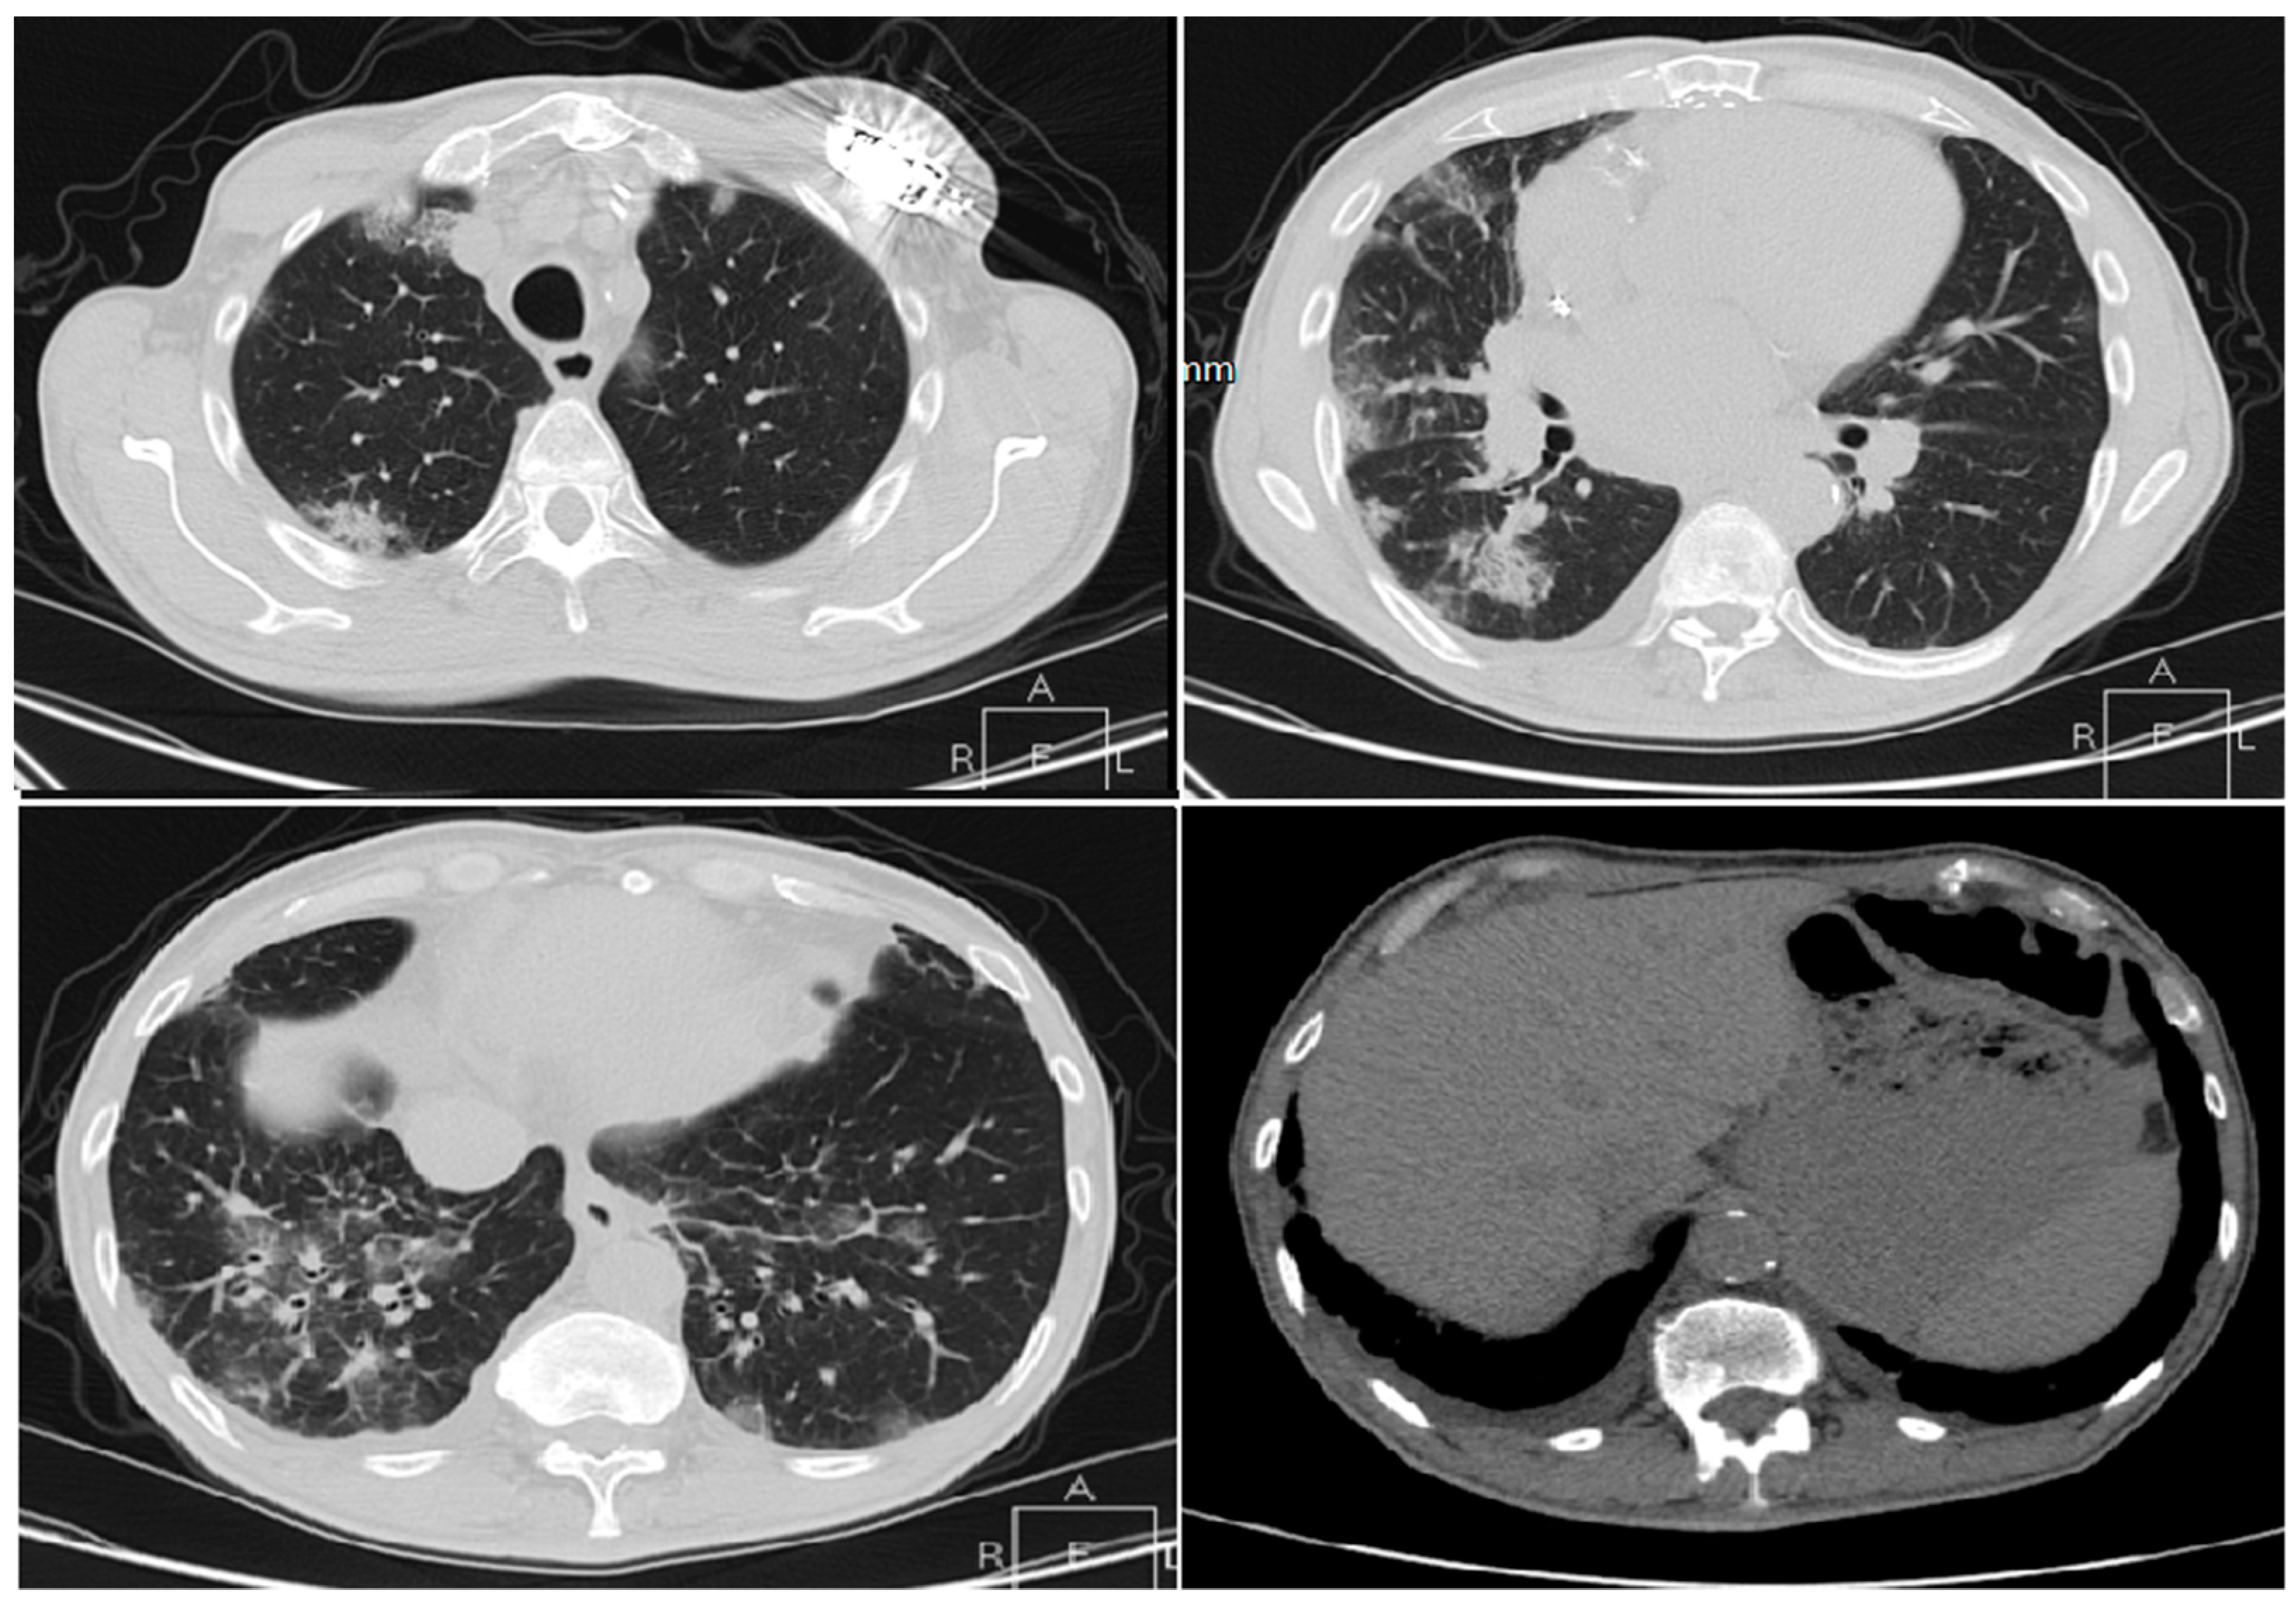

3.1.1. Cases Reports from Iran

Case 1

Case 2

Case 3

Case 4

Case 5

- Mahdavi, A.; Khalili, N.; Davarpanah, A.H.; Faghihi, T.; Mahdavi, A.; Haseli, S.; Sabri, A.; Kahkouee, S.; Kazemi, M.A.; Mehrian, P.; et al. Radiologic Management of COVID-19: Preliminary Experience of the Iranian Society of Radiology COVID-19 Consultant Group (ISRCC). Iran. J. Radiol. 2020. [Google Scholar] [CrossRef]

- Pan, Y.; Guan, H. Imaging changes in patients with 2019-nCov. Eur. Radiol. 2020. [Google Scholar] [CrossRef]

- Ng, M.-Y.; Lee, E.Y.P.; Yang, J.; Yang, F.; Li, X.; Wang, H.; Lui, M.M.-S.; Lo, C.S.-Y.; Leung, B.; Khong, P.-L.; et al. Imaging Profile of the COVID-19 Infection: Radiologic Findings and Literature Review. Radiol. Cardiothorac. Imaging 2020. [Google Scholar] [CrossRef]

- Zu, Z.Y.; Jiang, M.D.; Xu, P.P.; Chen, W.; Ni, Q.Q.; Lu, G.M.; Zhang, L.J. Coronavirus Disease 2019 (COVID-19): A Perspective from China. Radiology 2020. [Google Scholar] [CrossRef]